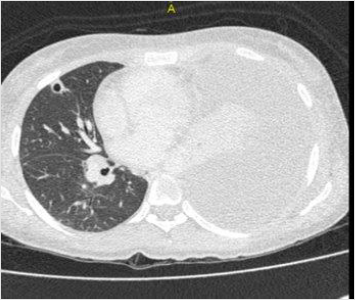

A chest radiograph showed large free left pleural effusion. Blood cultures were collected and Piperacillin-tazobactam was initiated for sepsis. The patient was submitted to computed tomography (CT) image of neck and chest that showed collection on the left side of neck spreading from the parapharyngeal space to the supraclavicular region. The left internal jugular vein could not be visualized because bulky collection was hindering it. Lung CT images showed up large left pleural effusion and multiple bilateral pulmonary nodular opacities, some excavated, with soft tissue density measuring 8 to 13mm, suggesting an embolic origin (Figure 1). Abdomen and pelvis CT demonstrated an unexpected iliopsoas abscesses, mainly on the right side. The patient was promptly submitted to needle aspiration of cervical mass and diagnostic thoracentesis, but later the exudative pleural effusion was drained. Doppler ultrasound of cervical mass and veins revealed thrombosis within left internal jugular vein. The patient proceeded to the operating room for neck and iliopsoas abscesses drainage. Cultures of neck collection, pleural effusion, iliopsoas abscesses and blood were carried out to detect common germs, fungi and mycobacteria. Despite the negative tests, classical clinical picture and the improvement with antibiotic were essential to make the diagnosis. Venous therapy was maintained for two weeks and oral therapy with metronidazole for complete six weeks. The young patient was discharged without residual disability.